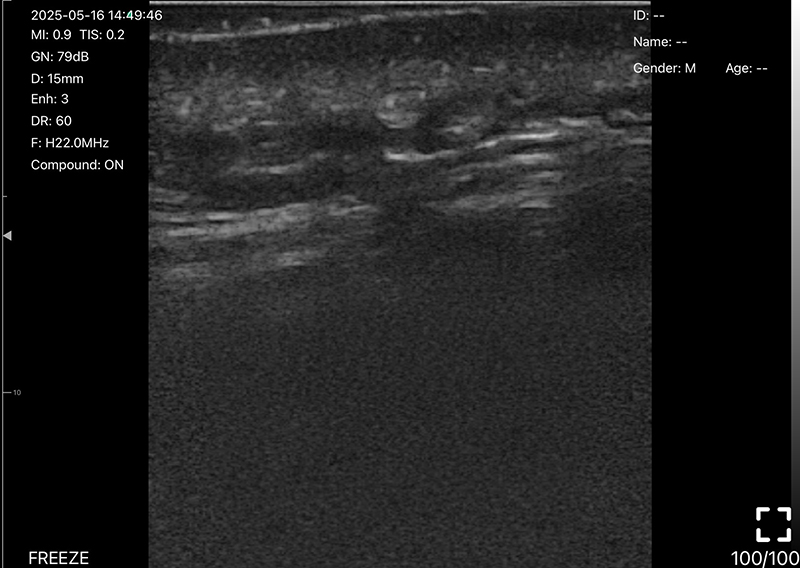

• 探头频率:10/13.2MHz

• B模式

增益:30db-105db

降噪:0-1-2-3-4

动态范围: 40-50-60-70-80-90-100-110

• 图像调节:增益、焦点、

反相脉冲谐波、降噪